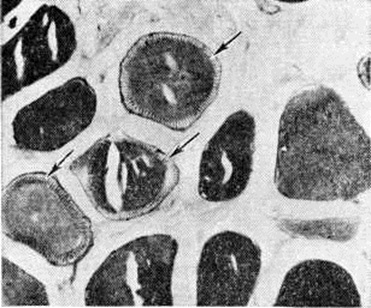

При патологоанатомическом исследовании в половине наблюдений определяется умеренная атрофия миокарда и кардиосклероз (смотри полный свод знаний). Отмечается разнокалиберность кардиомиоцитов, в части волокон — неправильное расположение миофибрилл. Электронно-микроскопическое исследование миокарда выявляет большое количество вакуолей в саркоплазматическом ретикулум и митохондриях, деструктивные изменения в миофибриллах. Нередки бронхоэктазы и эмфизема лёгких, которые связывают с гиповентиляцией и повторными инфекциями. Со стороны эндокринной системы отмечаются атрофия яичек и коры надпочечников, аденомы щитовидной железы. Изменения в нервной системе представлены атрофией двигательных нейронов спинного мозга, гидроцефалией со значительным расширением III желудочка головного мозга, атрофией периферических нервов. Однако ряд авторов указывают на отсутствие изменений в центральной и периферической нервной системе.